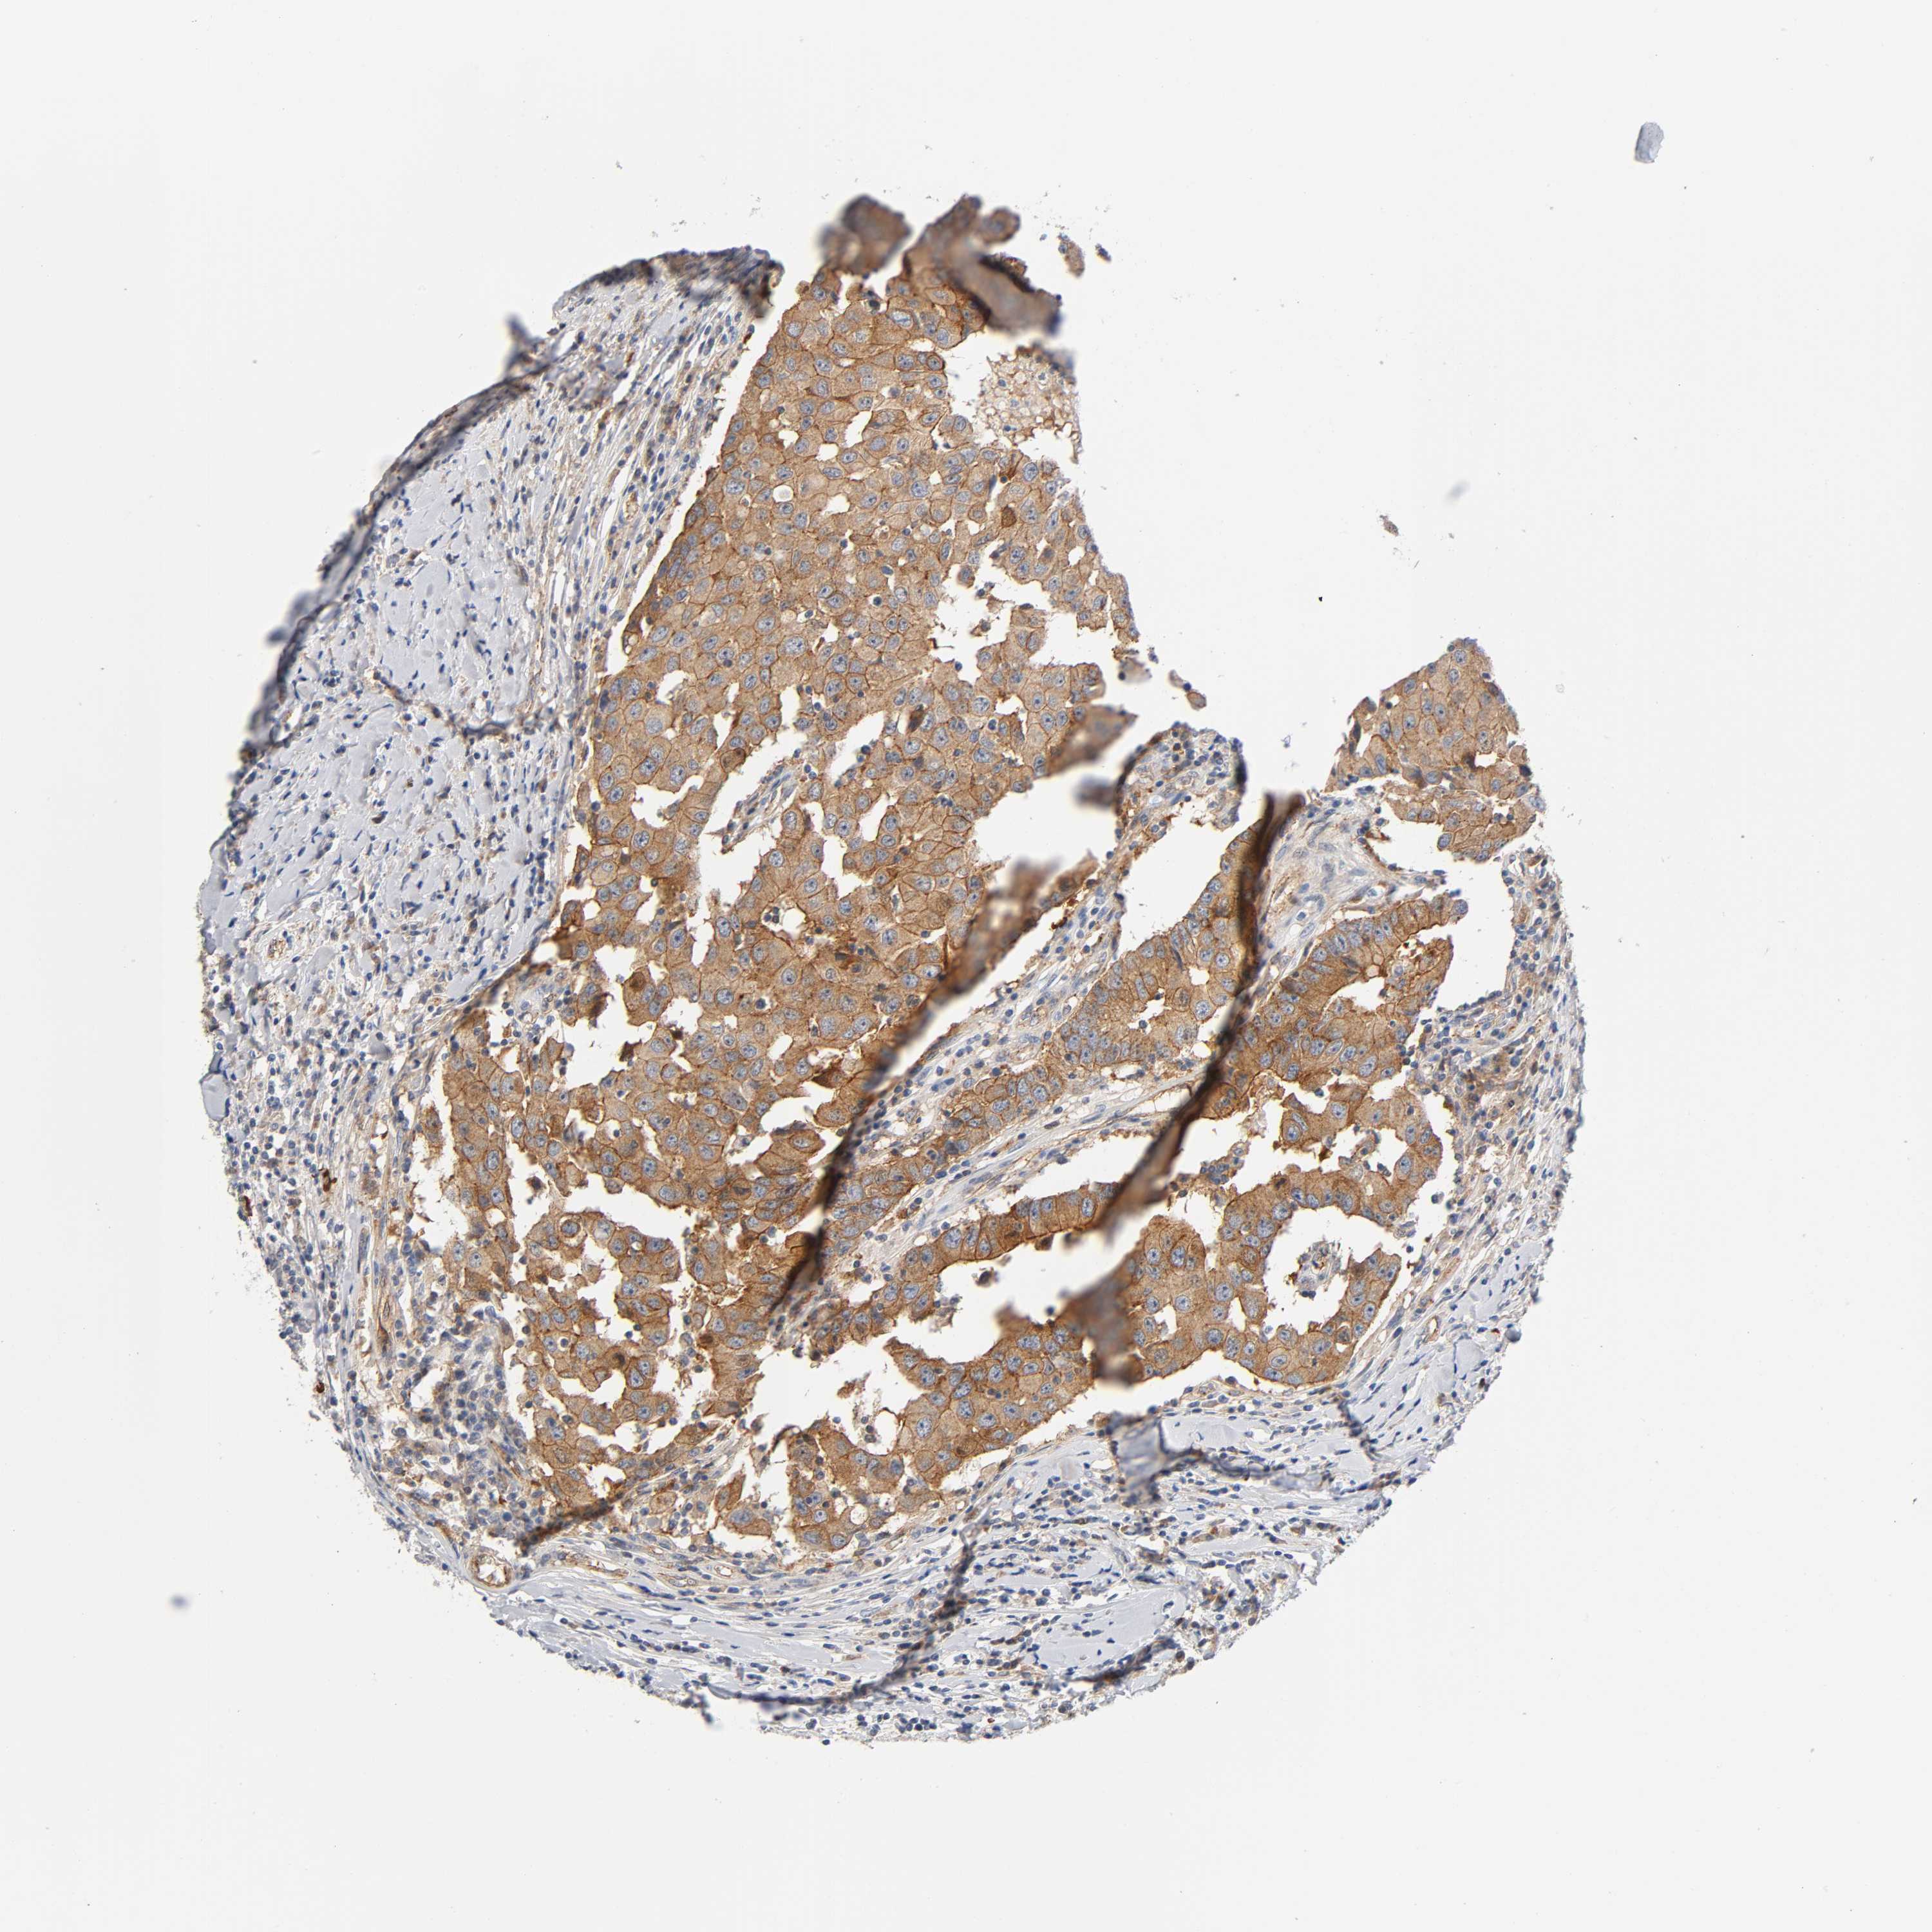

CANCER BREAST CANCER Show tissue menu

BRCA TCGA BRCA VALIDATION PROTEIN EXPRESSION